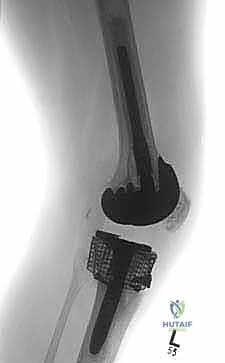

4. المخاريط والأكمام المعدنية المسامية (Porous Metaphyseal Cones & Sleeves)

هذه هي أحدث الثورات في عالم جراحة مراجعة المفاصل، وهي التقنية المفضلة لدى الأستاذ الدكتور محمد هطيف في حالات الفقدان العظمي الشديد (النوع الثاني والثالث من AORI). تُصنع هذه المخاريط من معادن عالية المسامية (مثل التنتالوم أو التيتانيوم المطبوع ثلاثي الأبعاد) التي تحاكي بنية العظم الإسفنجي.

تُزرع هذه المخاريط في التجاويف الكبيرة في قصبة الساق، وبفضل مساميتها العالية، ينمو عظم المريض الطبيعي داخل مسام المعدن (Osseointegration)، مما يوفر ثباتاً حيوياً وميكانيكياً هائلاً ومستداماً مدى الحياة.

5. السيقان الممتدة (Intramedullary Stems)

في جميع حالات المراجعة تقريباً، لا يمكن الاعتماد فقط على الجزء العلوي من قصبة الساق للتثبيت بسبب ضعف العظم. لذلك، يتم استخدام مفاصل ذات "سيقان" معدنية طويلة تمتد داخل القناة النخاعية لعظم قصبة الساق (Diaphysis). تقوم هذه السيقان بنقل الضغط والوزن من المنطقة الضعيفة في الأعلى إلى العظم القوي في الأسفل، مما يحمي المنطقة المعاد بناؤها ويضمن استقرار المفصل.

الخطوة الخامسة: زراعة المفصل المراجع الجديد

يتم إدخال المكون الظنبوبي الجديد (Tibial Tray) مع الساق الممتدة (Stem) التي تدخل في القناة النخاعية. يتم تثبيت هذه الأجزاء إما بالضغط الميكانيكي (Press-fit) أو باستخدام الإسمنت العظمي في مناطق محددة. يتم تكرار نفس العملية لعظم الفخذ إذا لزم الأمر.